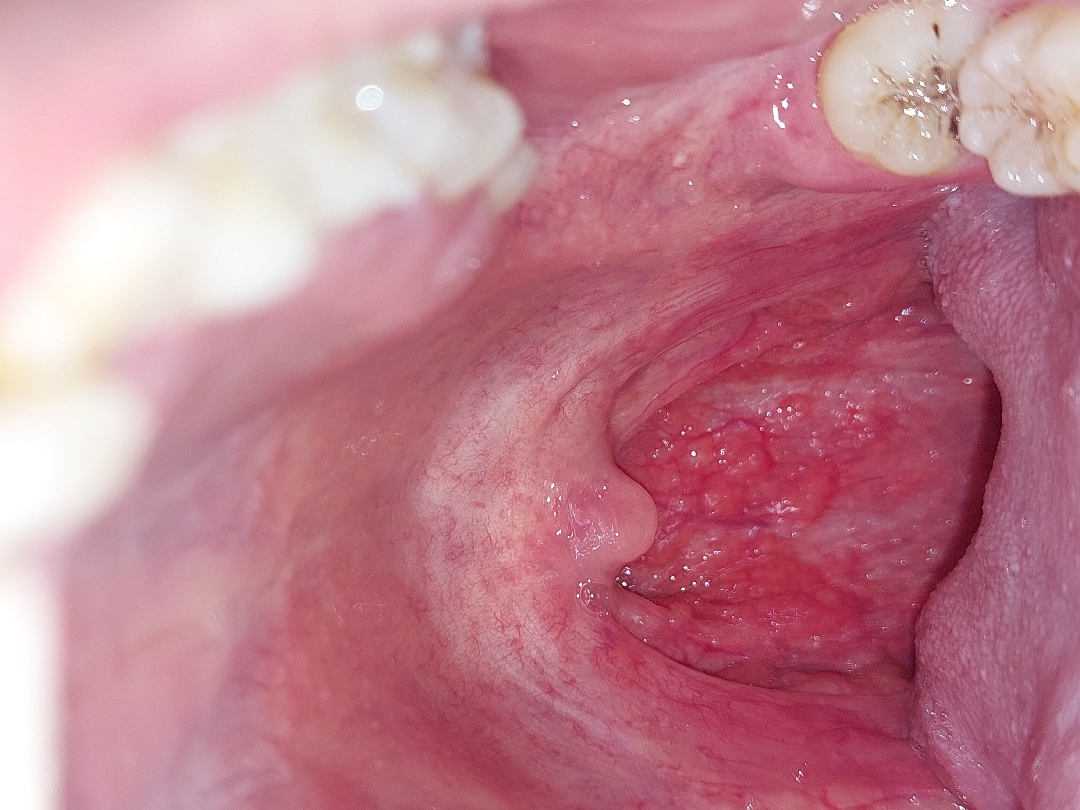

Hiện tại hình ảnh này không phải hình ảnh của sùi mào gà. Tổn thương là các hạt lympho trong viêm họng mạn tính. Đây là các tổ chức lành tính. Khi điều trị viêm họng các hạt này có thể nhỏ lại. Em nên điều trị chuyên khoa tai mũi họng.